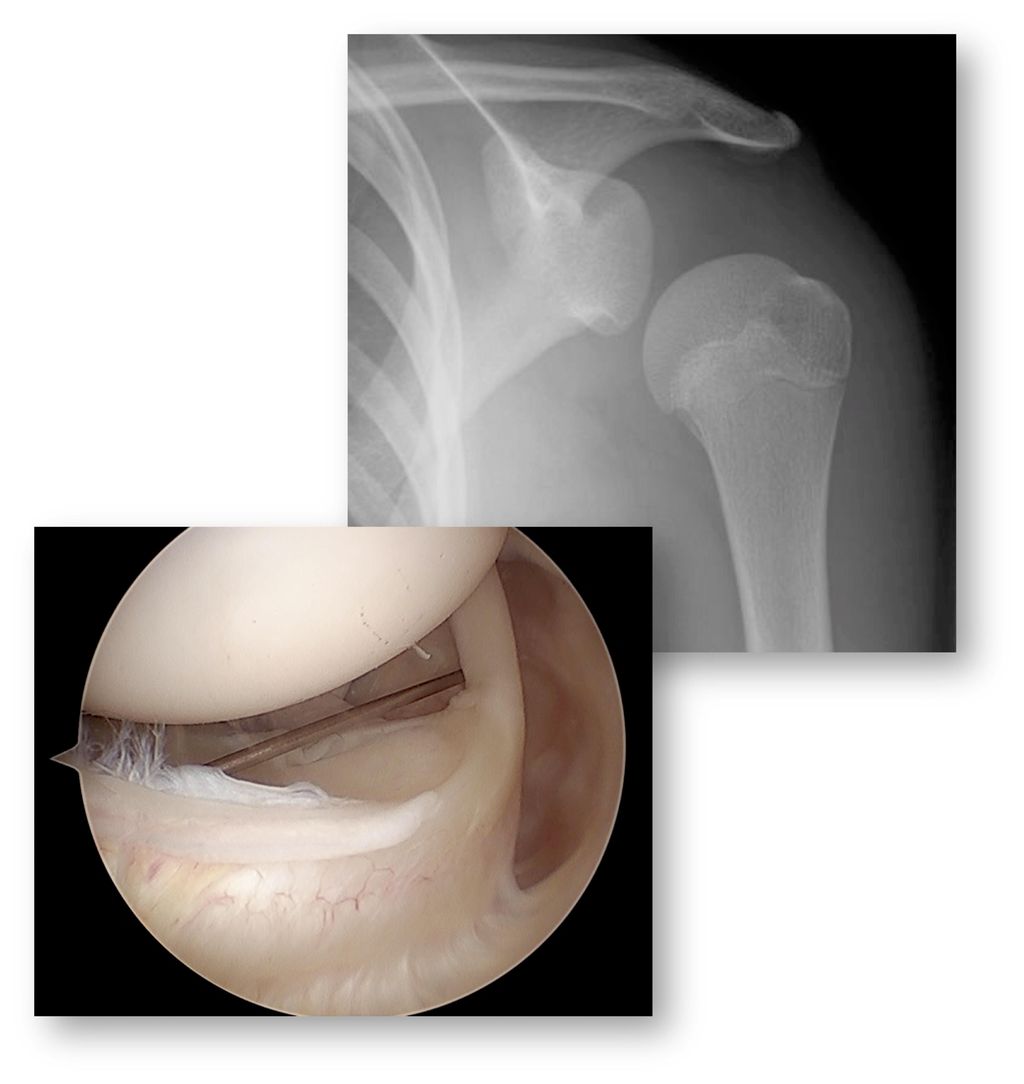

Das Hauptproblem ist die Tatsache, dass Instabilität eine funktionelle Problematik und nicht automatisch mit strukturellen Veränderungen assoziiert ist. Auf der anderen Seite können auch strukturelle Veränderungen auftreten, ohne dass eine Instabilität entsteht oder entstanden ist. So kann zum Beispiel die überweite Kapsel als kausale Pathologie für die multidirektionale Schulterinstabilität (MDI) am nativen MRI nicht beurteilt werden (Gefahr falsch negativ). Auf der anderen Seite können zum Beispiel die Wachstumskerne am anteroinferioren Glenoid, die regelmässig bis spät in die zweite Dekade nicht fusionieren, als ossäre Bankert-Läsion fehlgedeutet werden (Gefahr falsch positiv) (Abb. 1).

Abb. 1: Der anteroinferiore Knochenkern des Glenoids fusioniert erst in der 2. Dekade und kann mit einer Bankart-Läsion verwechselt werden. Nach Sidhartan et al., Arthroscopy 2020